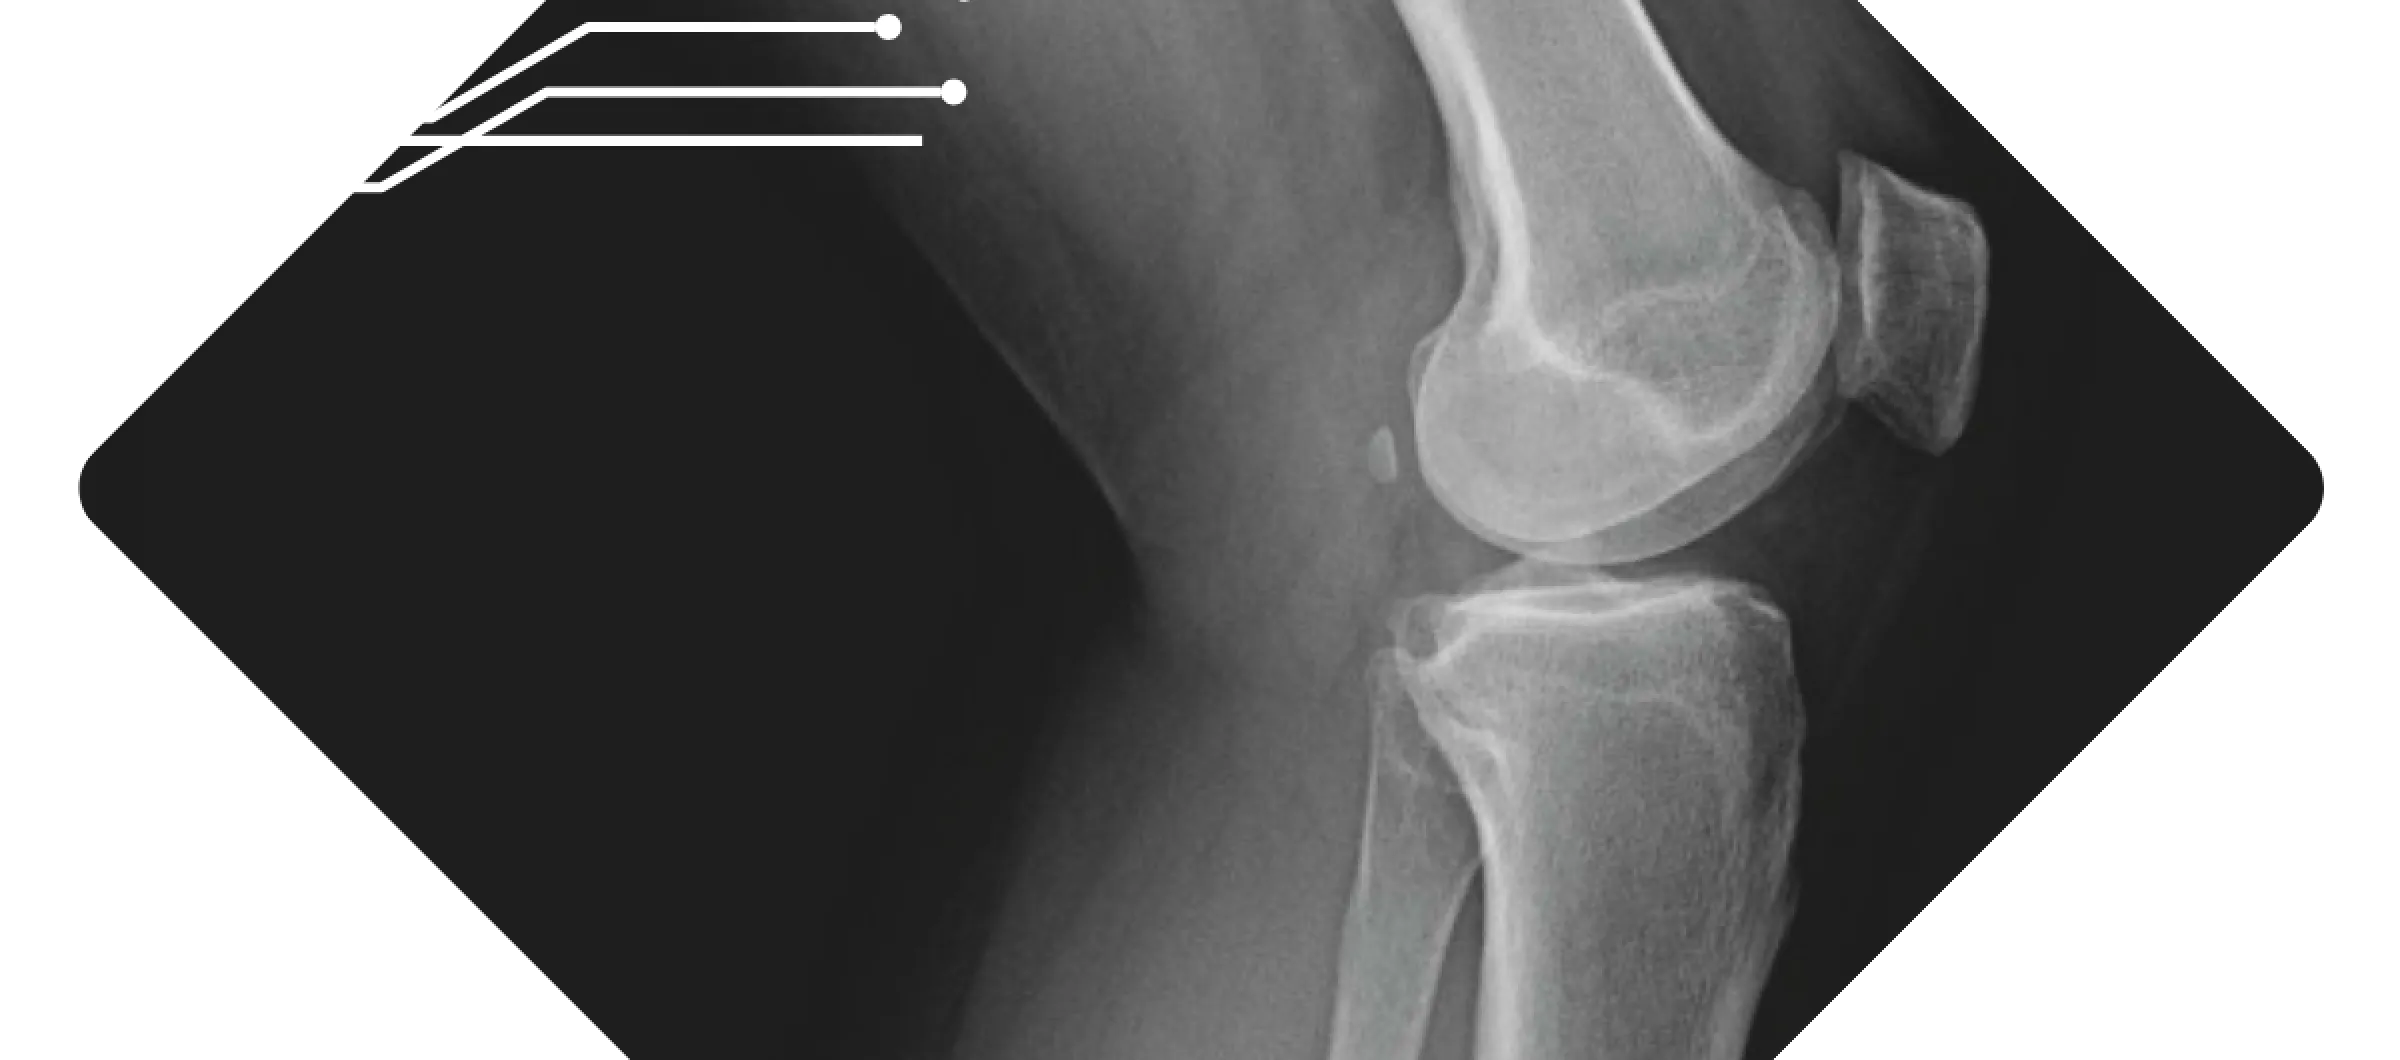

X-ray image showing a human knee joint with visible femur, tibia, and patella bones in a diamond frame.

We believe that the sooner you have answers, the sooner you can heal. Our practice maintains both digital X‑ray and mini‑fluoroscopy machines on‑site, which means we can capture high‑quality images during your appointment without sending you elsewhere. These machines are designed to deliver low‑dose radiation while providing clear, detailed images of bones and joints.

At our practice, your images are reviewed right away so you can talk through the findings and next steps before you head home. In orthopedics across the United States, requesting an X‑ray before your visit is considered standard care. It allows our specialists to see your bones and joints clearly and makes the best use of your time when you come in. We understand some people feel uneasy about imaging, but it's a routine part of musculoskeletal care that's focused on getting you the most accurate evaluation. If you are pregnant or scheduling an appointment for a child, please let us know; we'll coordinate with your doctor and take any extra precautions needed to keep you safe.

At Pacific Crest Orthopedics we have both X-ray and fluoroscopy machines in the office for quick diagnosis and evaluation of all orthopedic injuries. The machines are low radiation and give high-quality images. We can take immediate X-rays of most orthopedic injuries including injuries to the clavicle, shoulder, elbow, wrist, hand, finger, hip, femur, knee, tibia/fibula, ankle, and foot. Each of these can be taken during your appointment and then read promptly by the provider for an efficient diagnosis.

At Pacific Crest Orthopedics, we have advanced X-ray machines right here in our office that use very low radiation to produce clear, detailed images of your bones and joints. We can take X-rays of many areas, including your collarbone, shoulder, elbow, wrist, hand, fingers, hip, thigh, knee, shin, ankle, and foot, all during your appointment. This allows your doctor to quickly review the images and provide an accurate diagnosis so treatment can begin promptly.